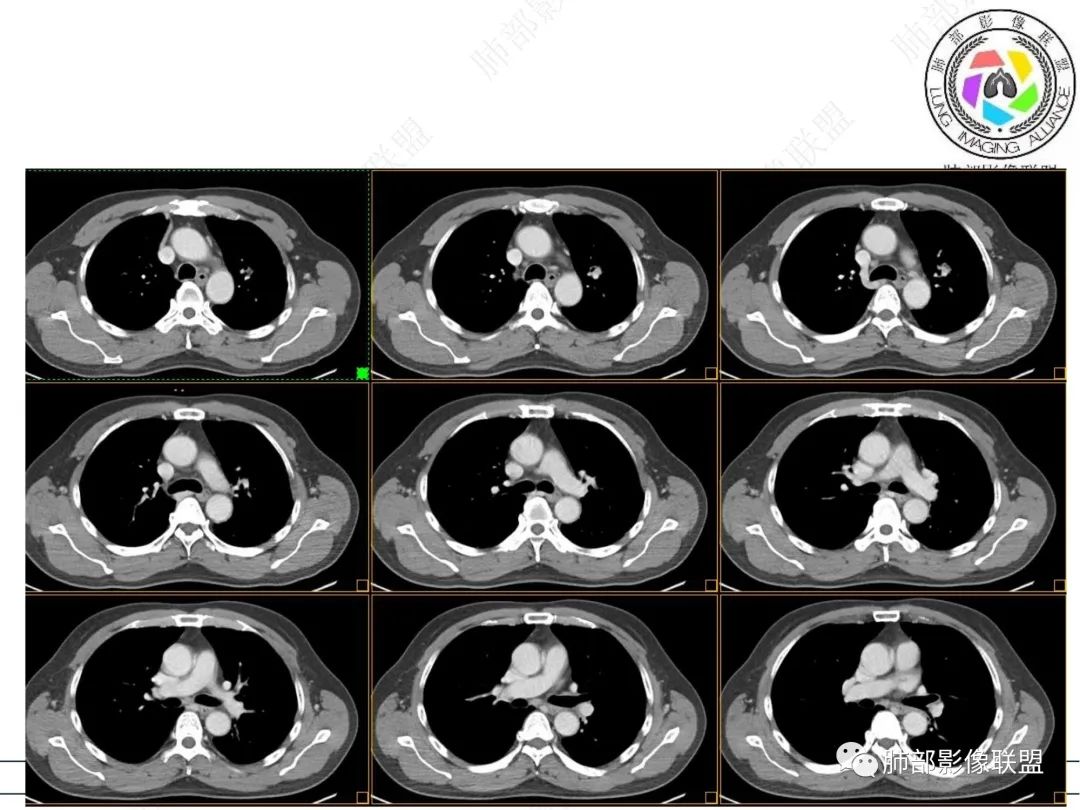

1、临床:57岁男性,3年逐步增大。孤立病灶持续三年原地坐大,符合肿瘤性病变,恶性程度不高或者早期进展缓慢。良性肿瘤常多年静止或进展极其缓慢。炎性病灶“星火”可以燎原,临床表现也会逐步加重。尽管继发性肺结核可以相对惰性,但病灶强化不明显,多结节、多卫星、多新旧不等,相对清楚硬朗。

2、病灶以实性密度为主,前、外侧蔓延,GGO部分边界清楚,部分欠清

支气管未见受明显侵犯,未见阻塞,壁增厚,狭窄或扩张。

软组织+重建;病灶实性部分不是类圆形,密度相对均匀柔和。

肺门区病灶与支气管关系不密切,强化显著、磨玻璃晕等等容易想到的是肺腺癌。而不首先考虑与支气管密切相关恶性肿瘤,如鳞癌、类癌、粘液表皮样癌等等。

1、连续3年观察,病灶逐步增大,符合惰性恶性肿瘤。2、支气管壁增厚,腔内内壁无变化——病灶长轴沿支气管周围蔓延;朝外走,内侧没有,提示病灶间质为主,与支气管无关。

3、GGO长期存在,朝外蔓延,支持恶性特点。

支持淋巴瘤的关键点:1、间质为主;2、与支气管无关;3、边缘GGO的长期存在支持恶性

因为与支气管无关不支持腺癌,还是要警惕淋巴瘤。